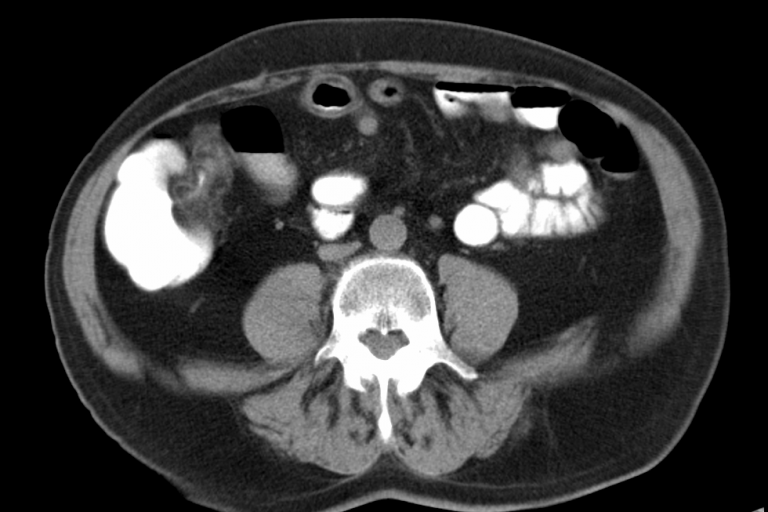

Die Magnetresonanztomographie (MRT) ist ein modernes, strahlungsfreies Bildgebungsverfahren, das vollständig ohne Röntgenstrahlen auskommt. Sie eignet sich in besonderem Maße zur detaillierten Darstellung von Weichteilstrukturen wie Gehirn und Rückenmark, Sehnen und Muskeln, Bandscheiben sowie inneren Organen wie Leber, Nieren, Bauchspeicheldrüse und Milz. Darüber hinaus lassen sich auch knöcherne Strukturen wie Wirbelkörper und Gelenke sowie deren Bestandteile…